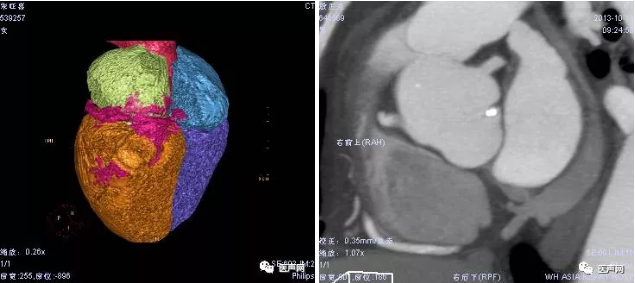

⊙ Echo:全心扩大,Lad 51mm,LVEDD 79mm,LVEF 26%经超声评估,室壁运动减弱,左右室间存在机械不同步

患者平卧位,接carto3标测系统,穿刺右侧股动脉,送4mm大头标测电极至左室,行左室三维激动标测,经左室三维激动标测显示,左室侧后壁为左室激动最晚部位,将大头标测电极放置该处,并X线下多体位投照,记录该位置,旨在评估激动最延迟区域是否有靶静脉覆盖,并指导左室导线靶向植入。